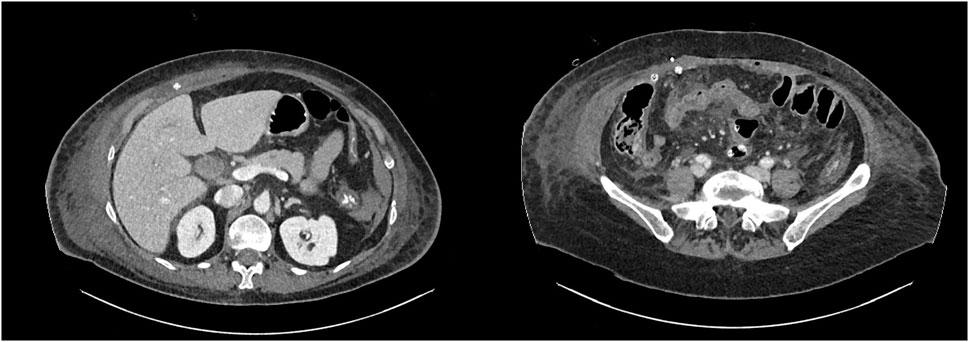

进行了紧急剖腹手术。放置伤口保护器后,发现胆汁性腹膜炎,由于创伤后空肠延迟穿孔,右肌后间隙广泛受累。进行了回肠-回肠吻合的肠切除术,并对涉及腹壁的坏死组织进行了细致的清创,包括右后直肌鞘的一部分。用生理盐水和消毒剂对空腔和肌后间隙进行彻底灌洗。在肌后间隙放置引流管(图2)。

图2 术后CT扫描,网状物上方肌后和皮下引流

使用小咬合技术和可吸收缝线实现了筋膜的初步闭合。由于筋膜的状态减弱,在这种情况下发生切口疝和腹部爆裂的风险很高,在彻底灌洗后,将浸有庆大霉素的可吸收生物合成网(BioA®9×15cm)贴在上面以加强中线。进行皮下引流。采用负压伤口治疗以降低伤口感染和裂开的风险。